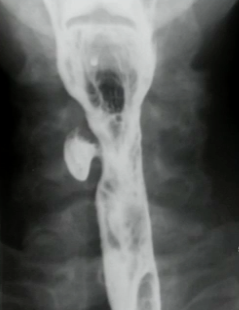

What is your diagnosis in this patient who presented with heart burn?

Sliding hiatal hernia. Note that the mucosal ring is > 2 cm superior to the diaphragm.